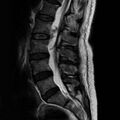

Within the spine, they most often occur in its thoracic part, although spinal chondrosarcomas represent only 7% of all these tumors. As in the case of osteosarcoma, they most often occur in the long bones. The therapy is primarily surgical, but chemotherapy or radiotherapy may be applied depending on the type and behavior of the tumor. [24][25][26]náhled|MRI – metastáza prsního karcinomu